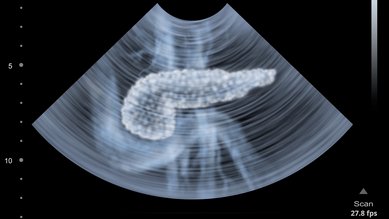

Pankreas kanseri

Almanya'da yılda yaklaşık 20.000 kişi pankreas kanserine yakalanıyor. Tümör genellikle geç teşhis edilir. Bu nedenle iyileşme şansı pek yoktur.